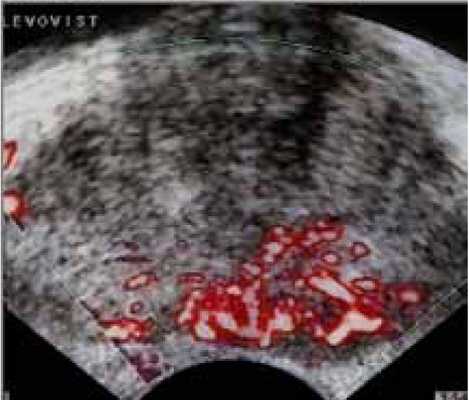

Однако, новые УЗ-технологии опровергают это мнение. Выполнение УЗИ также дает информацию о центральной, периферической части железы и о капсуле. УЗИ с допплеровским картированием, особенно при использовании эхоконтрастных средств, позволяет улучшить визуализацию и распространенность РПЖ (рисунки 2, 3).

Рисунок 3. Эхоконтрастное ультразвуковое исследование при РПЖ